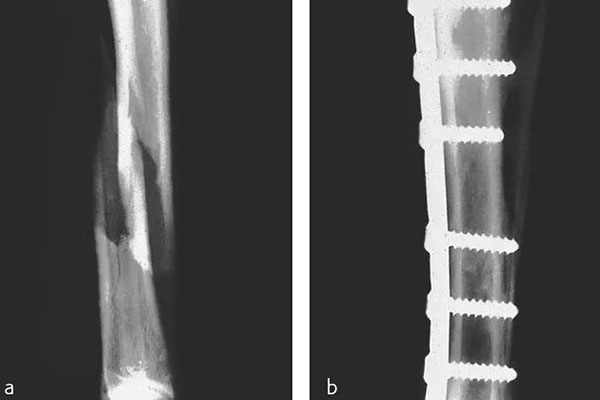

那在檢測(cè)的時(shí)候還需要看到植入物的情況,但由CFPEEK復(fù)合材料制成的零件通常具有放射透性,幾乎無法通過X射線檢測(cè)。就通過添加諸如鉭絲之類的X射線散射材料,可以使植入物變得可見??梢钥聪聢D展示了一個(gè)固定骨折骨頭的骨愈合板??梢钥闯?,通過設(shè)計(jì)已對(duì)放射密度進(jìn)行了定制,以便在盡量減少對(duì)骨折部位遮擋的同時(shí)可視化組件。重要的是,實(shí)現(xiàn)X射線可見性的同時(shí)也能保持清晰的MRI圖像。